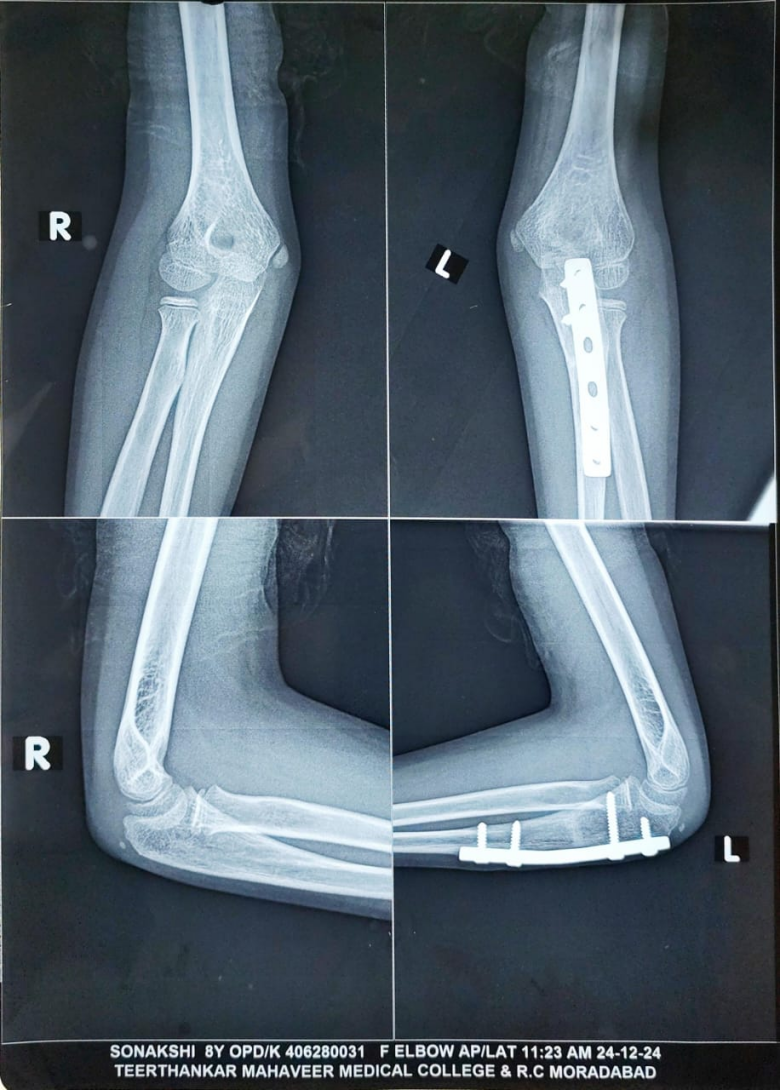

Radiographs of the left forearm and elbow (anteroposterior and lateral views) revealed a uniting fracture of the proximal ulna with anterior dislocation of the radial head (Fig. 1) – findings consistent with a Bado type I Monteggia lesion. Given the history of trauma, absence of early imaging, and delayed presentation, a diagnosis of neglected Monteggia fracture-dislocation was made. Advanced imaging was not done as the radiographs were indicative of a Monteggia lesion in a 1-month-old injury. Radiographs were analyzed by methods as described by Lincoln and Mubarak, including the ulnar bow sign and the radiocapitellar line of McLaughlin [7].

Figure 1: Monteggia fracture dislocation left elbow (1-month-old).